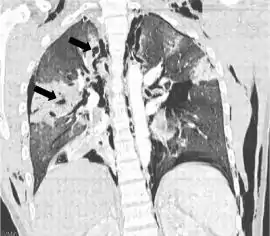

![]() TC coronal que muestra radiolucencias (áreas pálidas en la radiografía) en el pulmón causadas por laceraciones pulmonares ubicadas a la izquierda de la imagen (flechas negras) | ||